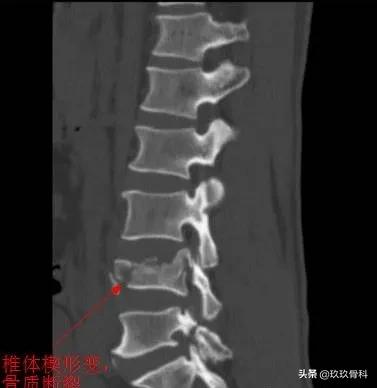

- (2) 椎体前缘骨质增生,与椎体紧密相连,边缘锐利,椎体前缘无缺损区;